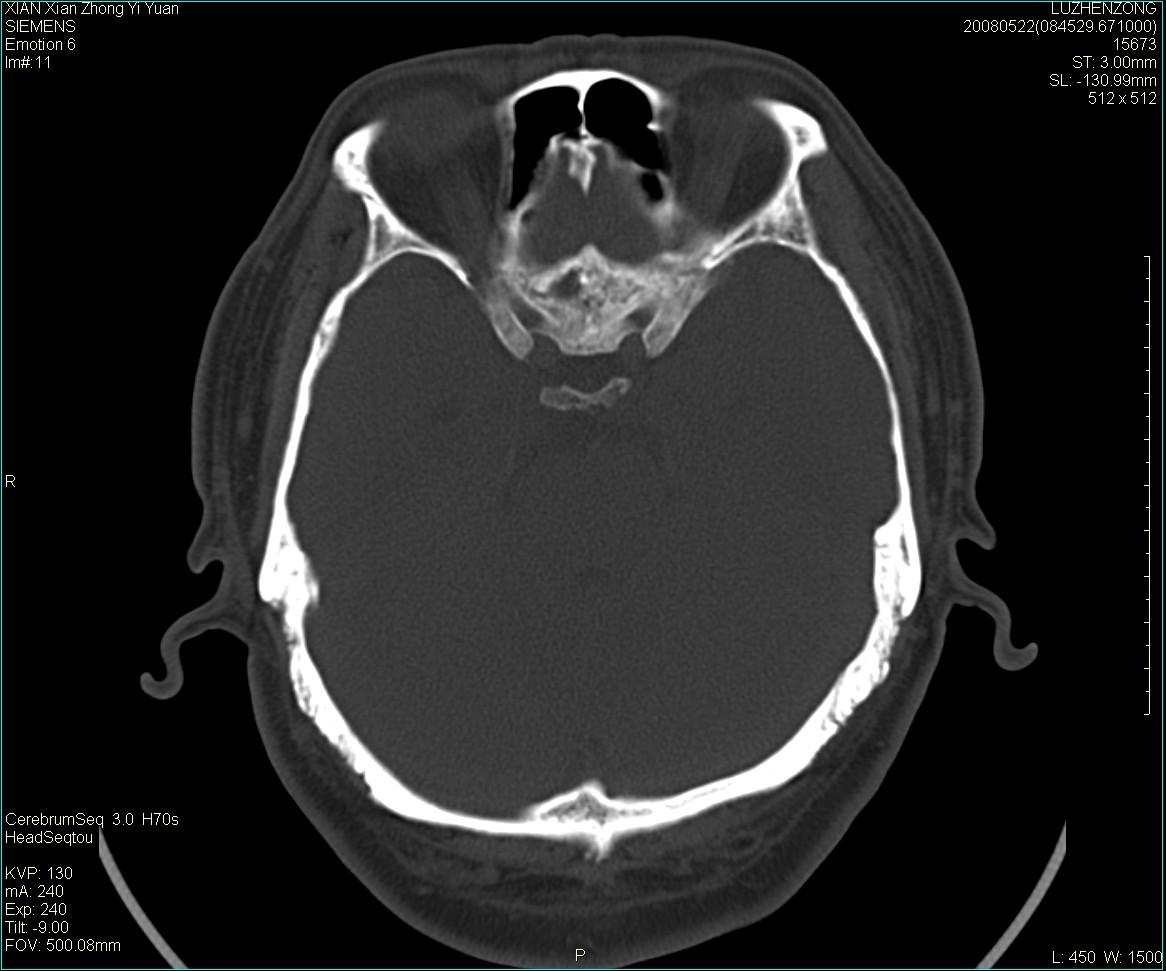

以下是引用gaoshengjiang在2008-5-28 19:06:00的发言:[br]考虑来源于蝶骨前床突区骨软骨瘤。

以下是引用卜一在2008-5-28 20:46:00的发言:[br]中颅窝“骨纤维异常增殖症”。不除外考虑来源于蝶骨前床突区“骨软骨瘤”。[br]

以下是引用liangshusheng在2008-5-28 20:13:00的发言:[br]单骨病变,考虑骨化性纤维瘤。